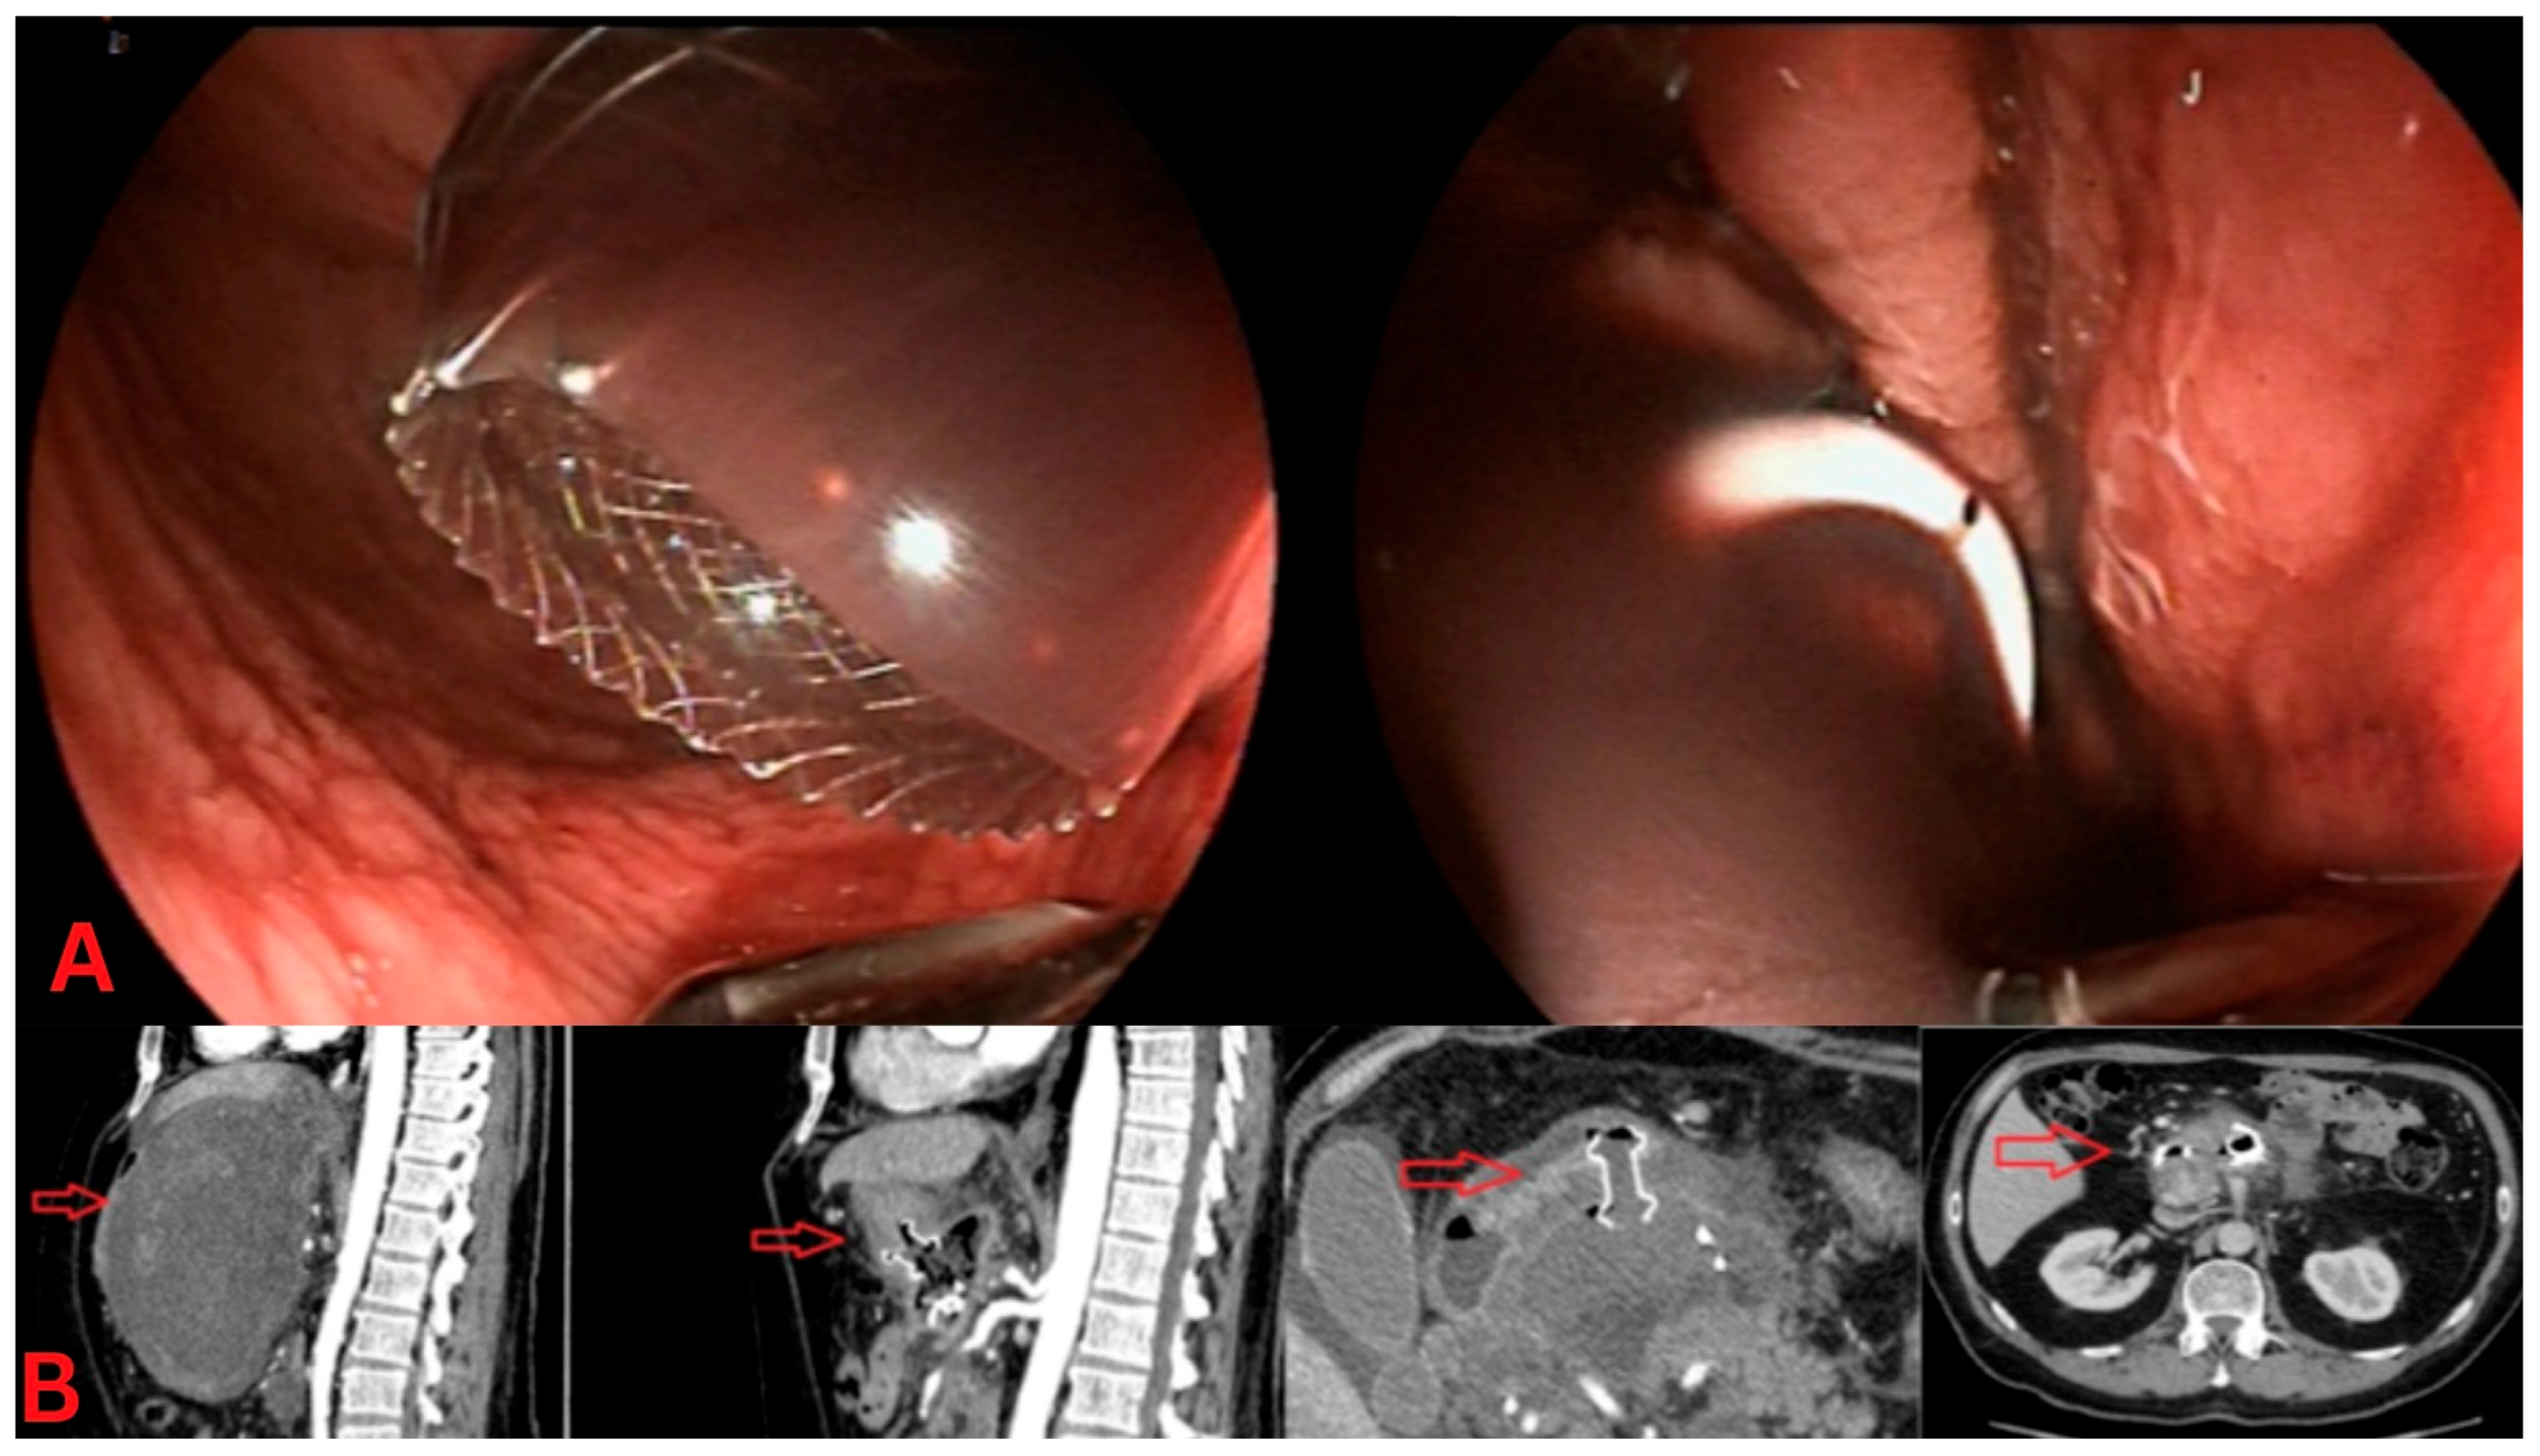

Figure 2. Dual-gate drainage for peripancreatic collections. (A) Endoscopic view: The left panel shows a lumen-apposing metal stent (LAMS) placed for drainage of a sizeable peripancreatic collection, providing a wide conduit for necrotic material to exit. The right panel displays a double-pigtail plastic stent, placed as a secondary drainage method, to offer additional decompression of the collection. (B) CT imaging: The sagittal CT view (left) highlights a dual-gate drainage approach, with a visible LAMS (red arrow) in place. The axial CT image (right) further illustrates the positioning of both the LAMS and pigtail stents, confirming adequate drainage of the peripancreatic fluid collection.